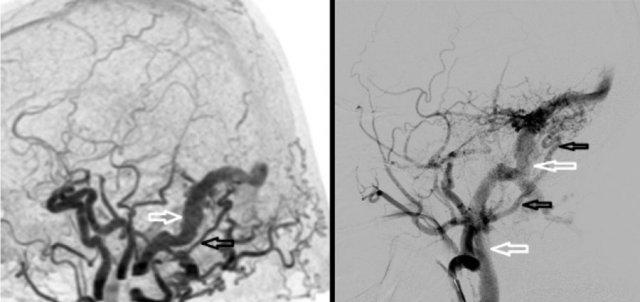

Rò động-tĩnh mạch màng cứng (dAVF) nằm ở xoang sigma phải được xác định bằng 4D-CTA và DSA.

4D-CTA bên trái, hình ảnh MIP trừ nền theo chiều bên cho thấy ngấm thuốc sớm bất thường của xoang sigma (mũi tên trắng) phù hợp với dAVF.

Động mạch chẩm phì đại được xác định là mạch nuôi (mũi tên đen).

DSA bên phải, bơm thuốc cản quang chọn lọc vào động mạch cảnh ngoài cho thấy động mạch chẩm phì đại và ngoằn ngoèo (mũi tên đen).

Dẫn lưu tĩnh mạch của xoang sigma vào tĩnh mạch cảnh (mũi tên trắng).